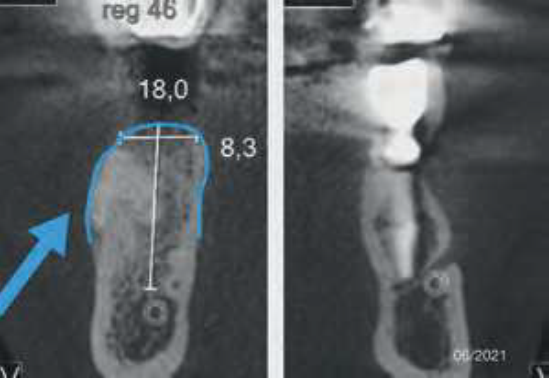

Após oito meses, o paciente realizou uma nova TCFC, sendo visualizado um ganho em volume na região do elemento 46 em comparação ao exame inicial (Figura 9). Seguiu-se então um segundo tempo cirúrgico. Após todos os passos de antissepsia e anestesia, foram realizados incisão em rebordo alveolar e descolamento para visualização do tecido neoformado. Em seguida, foi realizada a fresagem seguindo a sequência recomendada pelo fabricante para a inserção do implante dentário (4mm x 11mm, Maestro Hl Switch, Implacil De Bortoli), sendo iniciada com a fresa lança helicoidal subsequente das fresas cônicas com dimensões de 3,5mm x 11mm e 4mm x 11mm.